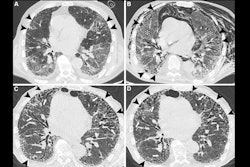

According to the findings, six out of the 14 (42.8%) children showed perfusion defects on Tc-99m MAA-SPECT/CT scans, without morphological alterations on coregistered CT.

Lung SPECT/CT scans with technetium-99m (Tc‐99m) macroaggregates (MAA) in three children with long COVID-19. No significant lung perfusion alterations were detected in a patient with long COVID-19 symptoms (A, D, F) on both axial hybrid images and functional slices (A, D). Conversely, imaging showed an area of mild hypoperfusion in the apical segment of the right upper lobe, clearly evident on both axial fused and functional slices in another patient (B, E; arrow). Finally, an area of moderate hypoperfusion was detected on a third patient, clearly evident on hybrid imaging, as well as on the functional slices (C, F; arrow), which is associated to a diffuse and heterogenous distribution of radiotracer in both lung parenchyma (*). All these abnormal findings do not correspond to parenchymal alterations on coregistered CT images (G, H, I). Image and caption courtesy of Pediatric Pulmonology through CC BY 4.0.Five of these six children were previously affected by a mild acute infection while one was asymptomatic during SARS-CoV-2 infection, the authors noted. During the follow-up, however, persisting symptoms (e.g., headache and shortness of breath during exercise) were detected in all six.